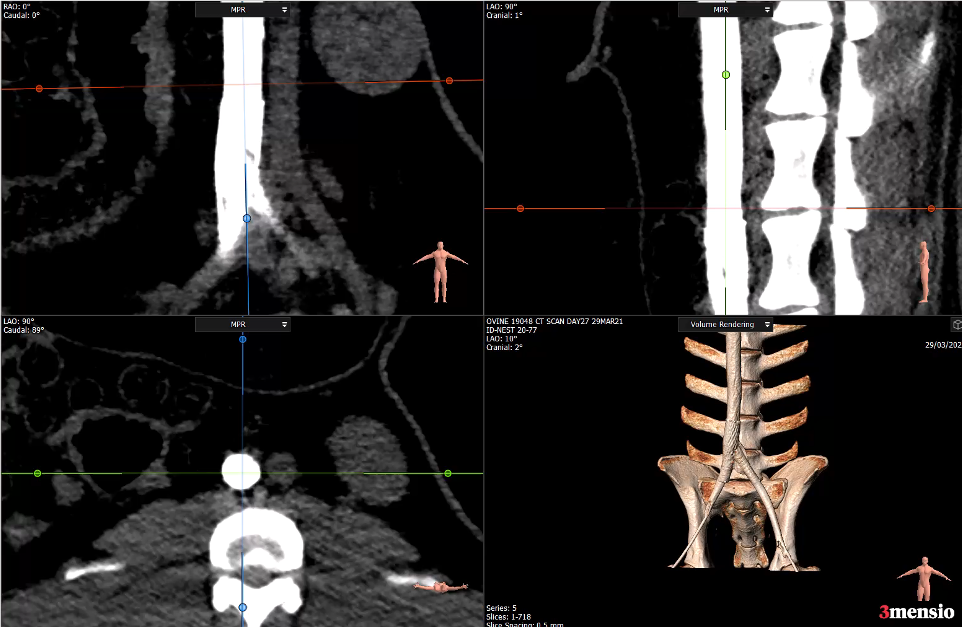

Le syndrome de Cockett, également nommé syndrome de May-Thurner, se traduit par la compression de la veine iliaque

commune gauche par l’artère iliaque commune droite contre les vertèbres lombaires.

Une échographie Doppler un scanner, une IRM , une échographie endovasculaire et/ou IVUS permettent de visualiser la compression, voire l’occlusion, de la veine iliaque par l’artère.

Afin de restaurer le drainage du sang, la veine est décomprimée par l’implantation du stent. En effet, par le biais d’une phlébographie (radiographie des veines), le chirurgien vasculaire réalise une dilatation de la veine avec un ballon et pose un stent pour maintenir la veine ouverte et rétablir un flux normal.

Grâce à sa conception renforcée, la technologie T-Stent d’ID NEST s’adapte aux contraintes mécaniques de la région iliaque.

Il restaure un flux veineux continu et stable tout en épousant les variations anatomiques propres au syndrome de May-Thurner.

Sa géométrie optimisée permet une implantation précise et durable.

La technologie T-Stent utilise un design auto-expansible robuste permettant une apposition homogène sur la paroi veineuse.

Sa structure assure une expansion régulière et stable, indispensable pour neutraliser l’effet de compression exercé par l’artère iliaque.

Il rétablit ainsi un flux sanguin continu et réduit efficacement la stase veineuse.